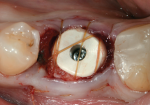

The placement of a provisional implant restoration delivers restorative design to the implant site. As with any provisional restoration, it can be either screw-retained or cement-retained. However, the main purpose of a provisional restoration is to aid in shaping and contouring the soft-tissue bed to develop the ideal emergence profile.7 Therefore, the implant must be placed at an adequate depth, and there must be enough soft tissue present to be molded and sculpted. One technique that has been utilized as an alternative to a provisional restoration is the use of a customized gingival former. This allows for the soft tissues to be formed without having a restoration involved that is in occlusion. This technique works well, but can be time-consuming chairside. The fabrication of a provisional restoration chairside using classical abutments and techniques can be technique-sensitive and time-consuming as well. The materials commonly used for these custom solutions are composite resin and polymethyl methacrylate (PMMA) acrylic, both of which are less than kind to the soft tissues.8 One recently developed restorative approach involves the use of polyether ether ketone (PEEK) as a material for both gingival formers and provisional abutments that have been pre-milled as stock abutments with generalized emergence profiles built into them (Figure 4 and Figure 5). This provides immense benefit in the ease of fabrication of provisional restorations as well as the use of prefabricated gingival formers. PEEK has been shown to be very kind to the soft tissues, and it is adjustable.9 Through the digital workflow, it is now possible to fabricate a screw-retained provisional restoration utilizing PEEK abutments prior to the surgery and deliver it intraorally with some slight modifications on the day of surgery (Figure 6).